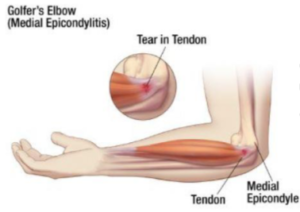

Epitrocleite (gomito del golfista/lanciatore)

Si tratta di una delle patologie più frequenti che interessano l’articolazione del gomito ed è rappresentata da un processo infiammatorio/degenerativo che interessa i tendini della parte interna del gomito. Si tratta quindi una tendinopatia che interessa, prevalentemente, il pronatore rotondo e il flessore radiale del carpo. L’epitrocleite colpisce con più frequenza l’arto dominante, più frequentemente pazienti tra i 35 e 50 anni, con un’incidenza più alta nel sesso maschile. E’ una problematica che colpisce sportivi (golfisti, ginnasti, tennisti che utilizzano prevalentemente il servizio e il diritto, giocatori di bowling, lanciatore di giavellotto), ma anche soggetti che, per lavoro, sollecitano ripetutamente i movimenti di presa e rotazione (carpentieri, elettricisti, imbianchini, muratori, ecc.).

La diagnosi è essenzialmente clinica attraverso un’attento esame obiettivo e in questi casi è sempre necessario verificare la presenza di segni e sintomi che indirizzino ad una sofferenza del nervo ulnare (in oltre il 40% dei casi associata ad una manifestazione dolorosa epitrocleare). Come per l’epicondilite, la risonanza magnetica e l’ecografia sono esami che servono solo per escludere lesioni ossee e tendinee.